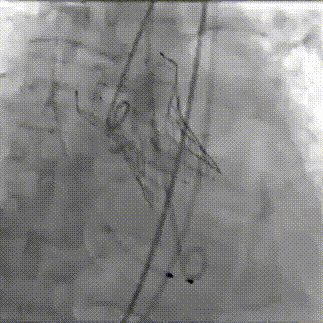

球囊预扩